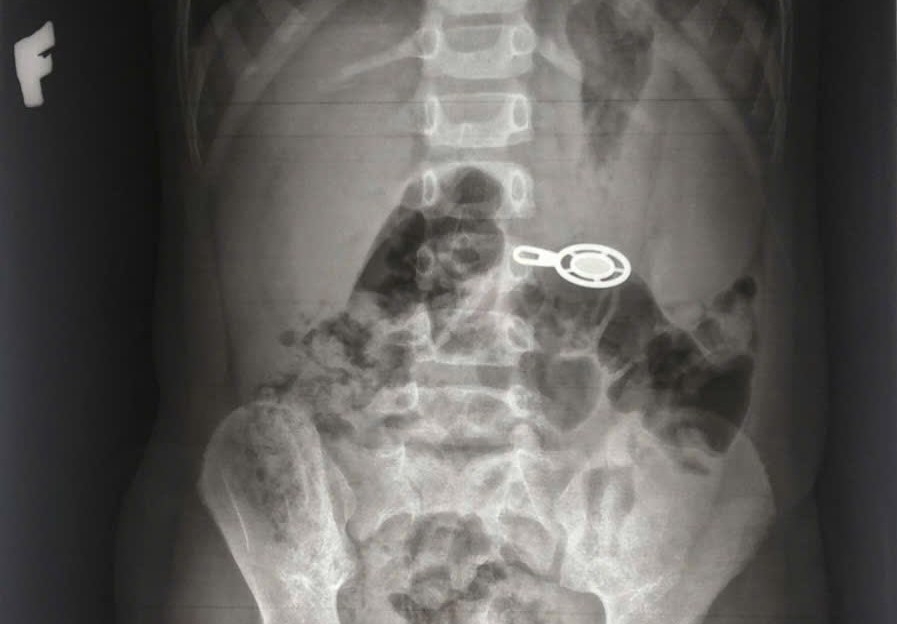

A l'hopital un film X-quaire a enregistre des images d'un corps etranger opere de la region abdominale transversale de la vertebre L3. Le patient a ete place en urgence endoscopique pour retirer un corps etranger de la voie digestive. Le corps etranger retire est un cadenas un fil de remorquage de sac a dos d'environ 2x3cm. Actuellement la sante de l'enfant est stable et il a ete autorise a sortir de l'hopital.